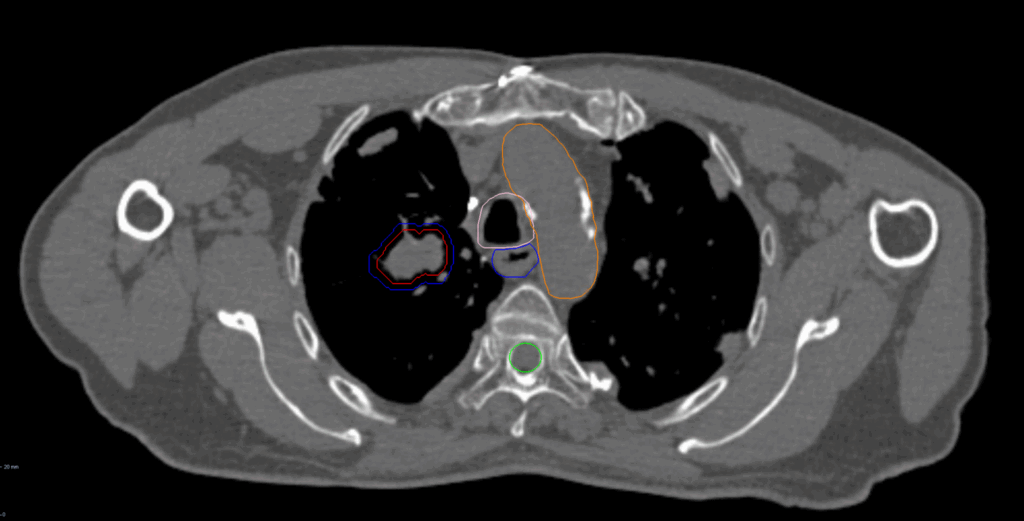

Planning CT Images